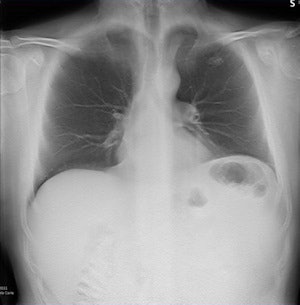

Digital tomosynthesis detected a left apical nodule in a 52-year-old male smoker. All images courtesy of Stephane Chauvie, PhD, and Dr. Maurizio Grosso.

Digital tomosynthesis detected a left apical nodule in a 52-year-old male smoker. All images courtesy of Stephane Chauvie, PhD, and Dr. Maurizio Grosso. CT confirmed the nodule in the patient and consequently he underwent surgery, which confirmed the tumoral nature of the nodule.

CT confirmed the nodule in the patient and consequently he underwent surgery, which confirmed the tumoral nature of the nodule."We have very preliminary data, but we believe digital tomosynthesis is a quite good method of detection for nodules," Grosso said.